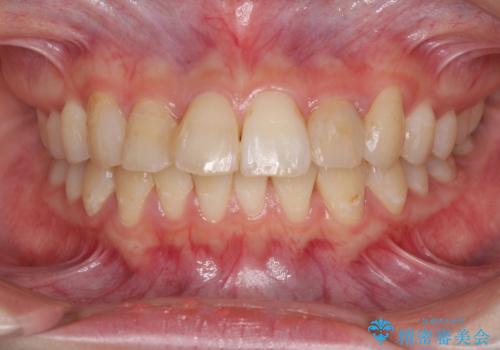

- コンポジットレジンによる治療で継ぎ接ぎだらけになってしまった前歯を綺麗にしたいとのことで来院された患者様です。

必要に応じて根管治療を行い、前歯6歯をオールセラミッククラウンで補綴することとしました。

治療途中に出産を迎えるため、下顎前歯のデコボコを部分矯正で改善し、上下前歯を綺麗に仕上げることとしました。